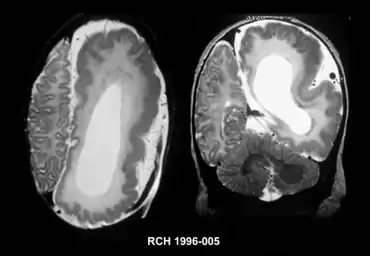

| Left-sided hemimegalencephaly in a person with neurofibromatosis[1] | |

Hemimegalencephaly (HME), or unilateral megalencephaly, is a rare congenital disorder affecting all or a part of a cerebral hemisphere.[2] It causes severe seizures, which are often frequent and hard to control. A minority might have seizure control with medicines, but most will need removal or disconnection of the affected hemisphere as the best chance. Uncontrolled, they often cause progressive intellectual disability and brain damage and stop development.[3]

It should be suspected in infants or children with intractable, frequent seizures.[4] On a CT scan, the affected part is distorted and enlarged.[9] It can be diagnosed prenatally, but a lot of cases go undiagnosed until seizures begin. Ultrasound can display asymmetrical brain hemispheres.[5]